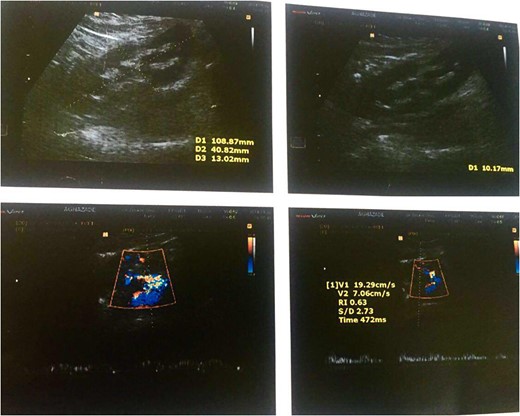

A ureteral catheter was inserted. A drainage tube was inserted to drain any possible bleeding from the operation site and then the surgical wound was closed. The patient was discharged in a good general condition after 3 days and the drainage tube removed. The ureteral stent was removed 4 weeks later by cystoscopy under local analgesia. An ultrasound imaging study of the genitourinary system 8 months into the patients follow up showed normal size, echo and cortical thickness in the operated kidney after renal autotransplantation.

Gray-scale ultrasonography of the patient's transplanted kidney 8 months after surgery.